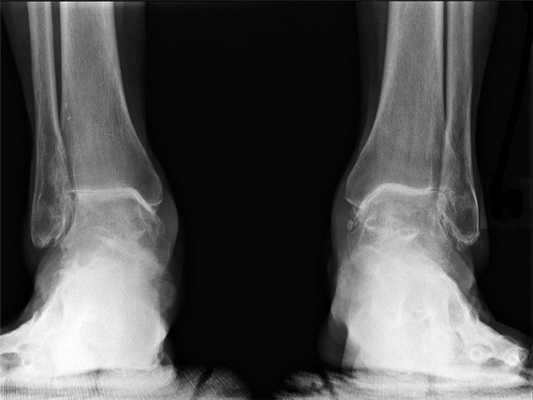

(Слева) Рентгенография в ЗП проекции: измененное запястье с массивным образованием кист в ладьевидной, головчатой костях и дистальной части лучевой кости. Определяется полная утрата хряща в лучезапястном суставе и отсутствие полулунной кости. Такая картина может ошибочно быть принята за РА или пирофосфатную артропатию.

(Справа) Рентгенография в боковой проекции, этот же случай: округлый очаг повышенной плотности с ровным контуром, расположенный в задней части сустава. Этот силиконовый имплант полулунной кости был установлен вследствие некроза полулунной кости, но в данный момент наблюдается его дислокация и вызванный им массивный остеолиз. (Слева) Рентгенография в ЗП проекции: резекция кости-трапеции и ее замещение силиконовым имплантом с ножкой, выступающим только в первую кость пясти. Это уже начало несостоятельности импланта, так как отмечается его подвывих радиально и разрушение ладьевидной кости. Обратите также внимание на резорбцию кости в области ножки импланта.

(Справа) Фронтальная STIR МР-И области ладонной поверхности запястья: распространенный синовит. Это реакция на силиконовый имплант кости - трапеции. Обратите внимание на фрагменты, часто визуализирующиеся прилегающими к импланту. (Слева) Рентгенография в ЗП проекции: удаление костей проксимального ряда запястья по поводу остеонекроза ладьевидной кости и вторичного остеоартрита. Определяется сращение кости-трапеции и трапециевидной кости. Обратите внимание на просветление в области выемки трансплантата в дистальной части лучевой кости.

(Справа) Рентгенография в ЗП проекции: резекция полулунной кости по поводу остеонекроза. Определяется сращение ладьевидной и головчатой костей, выполненное для предотвращения проксимальной миграции головчатой кости. Остеотомия дистальной части лучевой кости была ранее выполнена с целью удлинения.